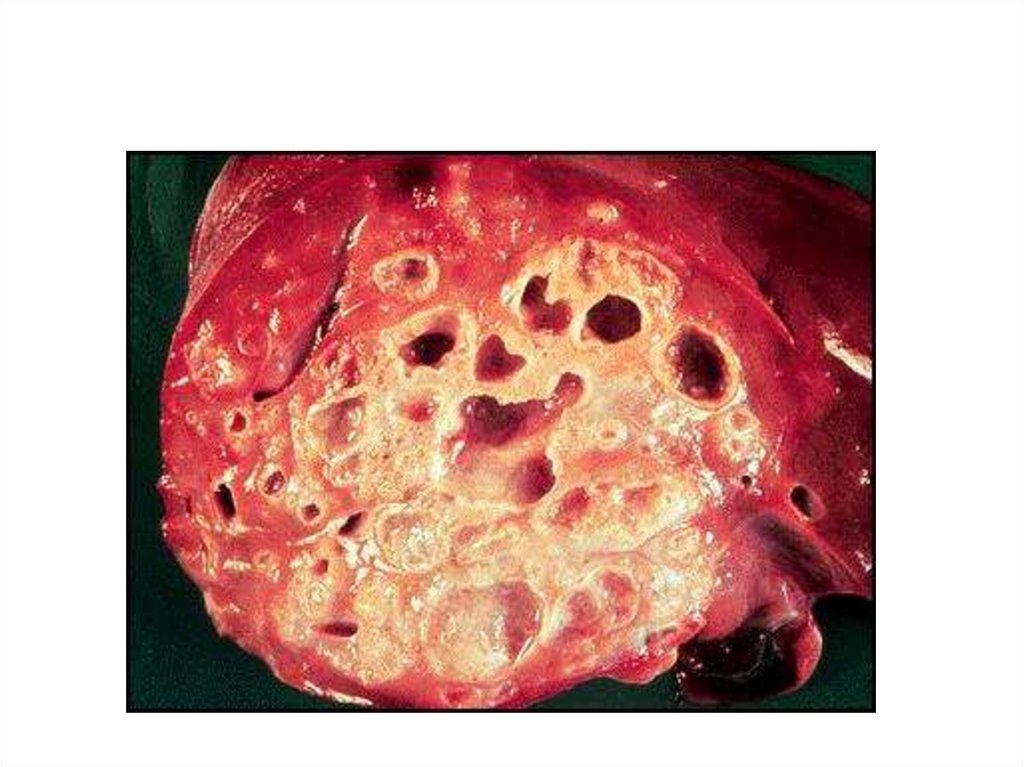

Эхинококкозы. Альвеококк

Альвеококк